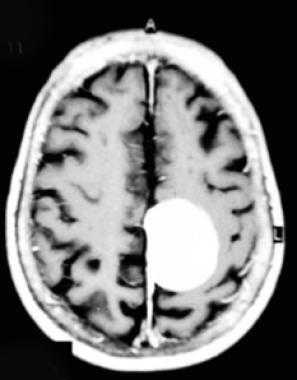

Парасагиттальная менингиома на МРТ с контрастным усилением. Видно гомогенное округлое образование, активно накапливающее контрастное вещество.

МРТ головного мозга (С+). Объемное образование в теменной области слева, широким основанием прилежащее к мягкой оболочке